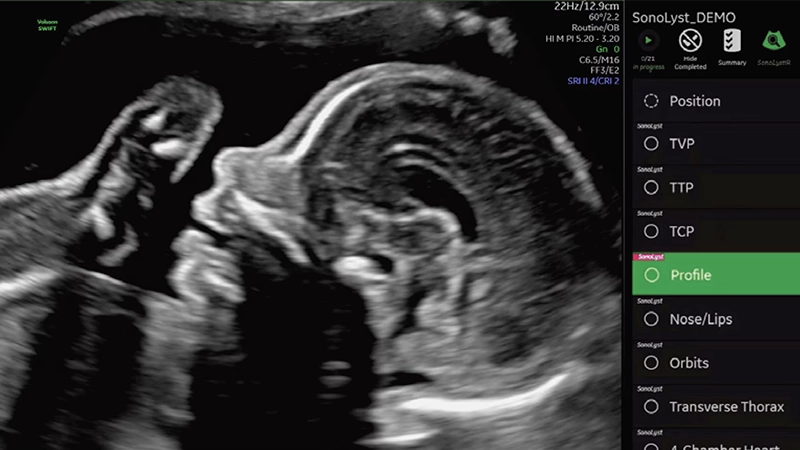

Ecografía